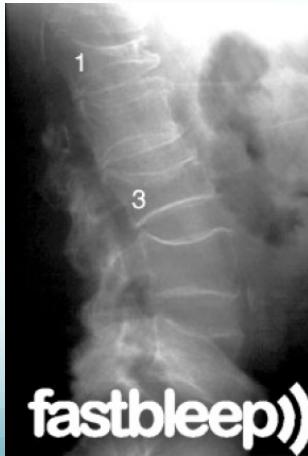

Burst Injury L-Spine

- Axial compression: shattered vertebral body

- Posterior fragments into spinal canal

- Usually unstable

- CT required

Burst Injury Classification

Is this a compression or a burst fracture?

- A burst fracture

- Why?

- Posterior displacement